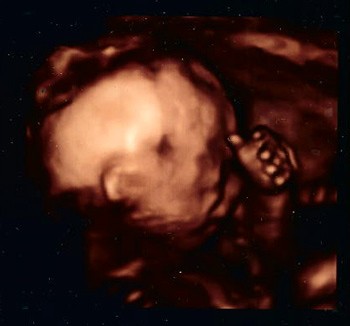

To i ja się pochwalę :zawstydzona/y:. Zdjęcia z 21 tygodnia i 4 dnia.

1a.jpg

2a.jpg

Siusiaka nie pokażę, bo może by się wstydził kiedyś :-D.